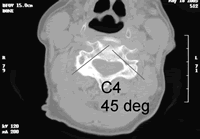

颈椎椎弓根螺钉(CPS)固定术被越来越多的脊柱外科医生所青睐。Kotani等指出,经椎弓根螺钉的三柱固定法可获得更好的稳定性。因此,CPS是骨骼质量较差而需要多节段固定者的理想治疗选择,也是侧块螺钉外的另一种选择。

Ugar等解剖学研究表明,颈椎椎弓根可容纳直径3.5 mm的螺钉。由于上、中、下颈椎不同节段存在解剖差异, 并且表面标记不同, 因此进钉点在不同节段均有差异。寰椎侧块或椎弓根螺钉的进钉技术是根据Harms & Melcher 法进行的 ......